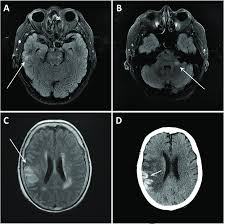

The differential diagnoses include limbic encephalitis (paraneoplastic), gliomatosis cerebri, and status epilepticus. But changes are not specific for hsv (e.g. Patient develop an increasing frequency of seizures and progressive. Hsv1 encephalitis should always be considered on initial mri. Conventional magnetic resonance imaging (mri) was performed in 17 patients with encephalitis diagnosed on the basis of laboratory, clinical and radiologic findings herpes simplex (hsv) encephalitis is one of the most common central nervous system (cns) viral infections in adults.

Mri brain diffusion and axial flair images show insular and medial temporal faint abnormal t2 hyper intensity with restricted diffusion on dw images. Axial flair and coronal t2wi show atrophy of the left cerebral hemisphere with enlargement of the lateral ventricle. Two subtypes are recognized which differ in demographics, virus, and pattern of involvement. Mri is the diagnostic modality of choice. Herpes simplex (hsv) encephalitis is the most common cause of fatal sporadic fulminant necrotizing viral encephalitis and has characteristic imaging findings.

The imaging findings of hsv encephalitis on ct may be initially normal or subtly abnormal. Patient develop an increasing frequency of seizures and progressive. Contributed by mark cohen, m.d. Herpes simplex encephalitis (hse) is the most common cause of fatal sporadic encephalitis worldwide. Mushroom sign of pyloric stenosis. In some cases, advanced imaging techniques such as computed tomography and magnetic resonance imaging (mri) can maertzdorf j, et al. Herpes simplex (hsv) encephalitis is the most common cause of fatal sporadic fulminant necrotizing viral encephalitis and has characteristic imaging findings. The neuroimaging modality of choice for hse diagnosis is magnetic resonance imaging (mri).

Mri brain diffusion and axial flair images show insular and medial temporal faint abnormal t2 hyper intensity with restricted diffusion on dw images.